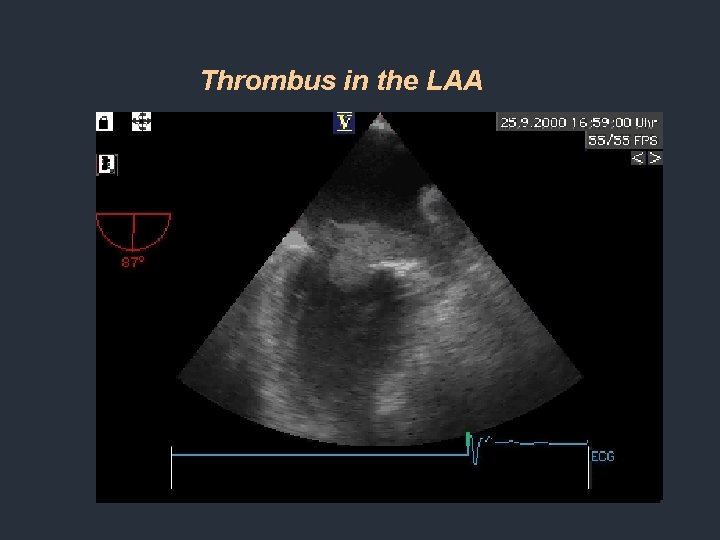

Thrombus in the LAA